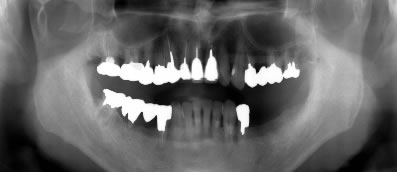

患者さんは48歳(女性)。全顎に義歯が装着されていましたが動かなくて、よく咬めるインプラント治療を希望の為来院。

写真5〜8はそれぞれ術前・後の左側口腔内写真とパノラマレントゲン画像です。

全顎にインプラントブリッジが装着され、審美的にセラミックで回復を施し、美しい笑顔が獲得された。さらに咀嚼機能も改善され患者さんも満足した症例である。

術後のパノラマレントゲン写真では、上顎10本、下顎8本のインプラントが埋入されている事が確認できる。